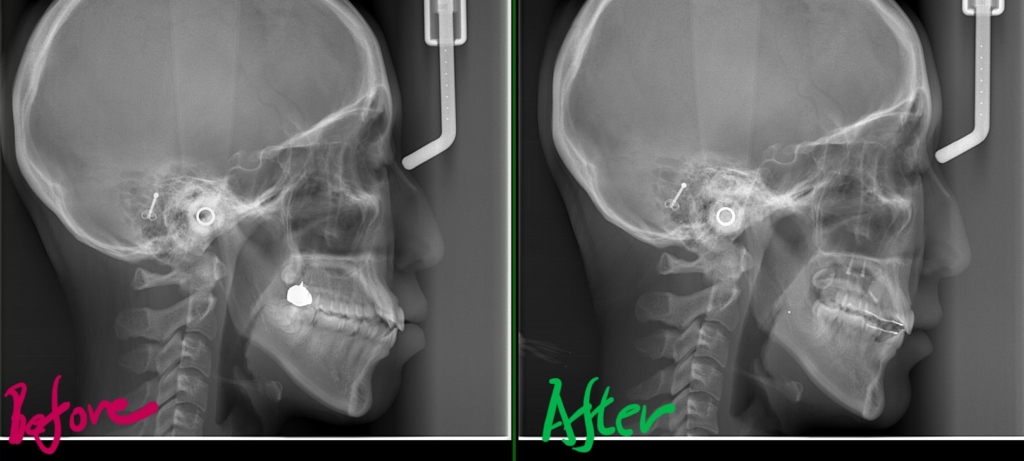

左側が矯正治療前、右側が矯正治療後

【Before】

レントゲン写真で確認すると、

【After】

矯正後の状態をレントゲン写真で確認すると、

最後に、矯正治療前後の「レントゲン写真」と「口元の写真」の比較をお見せしましょう。

それでは、その間の変化をレントゲン写真で見てみましょう。

右側が智歯を抜歯してアンカースクリューを併用しながら歯列全体を引っ込めた後の状態、